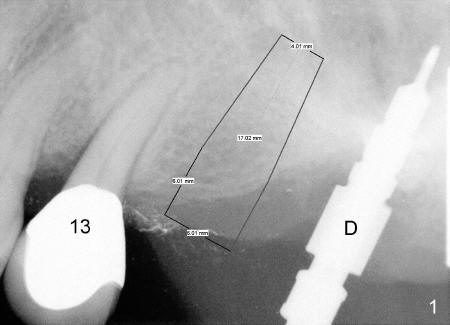

The implant at the site of #14 happens to be designed to be parallel to the tooth #13 and the drill at the site of #15 without too much thinking (Fig.1).